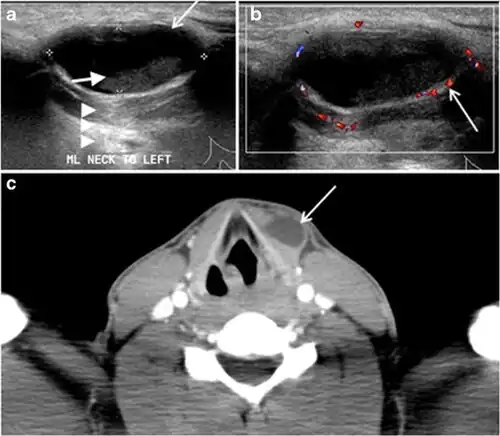

Fig. 2. A 51-year-old female patient post left hemithyroidectomy, with incidentally discovered a right thyroid colloid nodule on CT scan. an Enhanced axial CT scan of the neck demonstrates a well-defined, hypodense right thyroid nodule (white arrow) with no internal calcifications or cervical lymphadenopathy. b Transverse greyscale thyroid ultrasound demonstrates a well-defined, hypoechoic right thyroid lobe nodule with a central echogenicity including comet tail (ring down) artefacts (white arrow). No vascularity (not shown) or calcifications were detected.